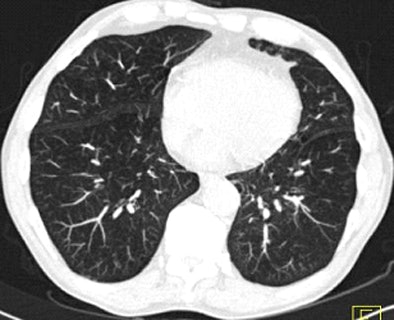

| Images above and below show a spiculated nodule measuring 169 mm3 at baseline low-dose CT screening. Bottom image, acquired four years after the baseline scan, shows that the nodule has resolved. All images courtesy of Dr. Rosemarijn Vliegenthart. |